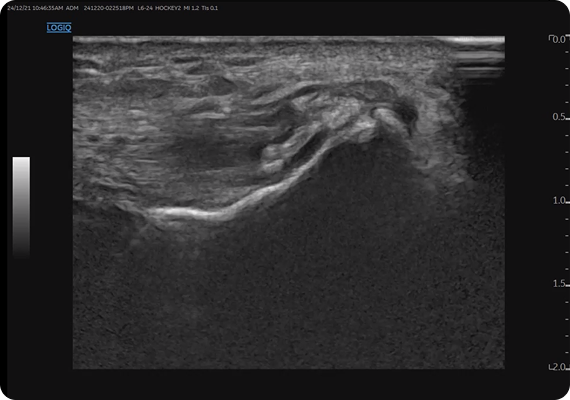

초음파 검사를 통해 황색인대, 관절외관, 신경근, 뿌리동맥 등 주요 구조물의 상태를 실시간으로 확인할 수 있습니다. 이를 바탕으로 SVN이 주행하는 ventral epidural space까지 정확히 파악하여 환자분의 상태에 맞는 치료 계획을 수립할 수 있습니다.

초음파 유도하 침도 요법은 섬유륜, 후종인대, 신경근 등 병변 부위를 직접 보며 시술할 수 있습니다. 이를 통해 추간공 협착, 후관절 유착, 근막성 통증을 함께 개선하고 신경의 gliding 기능 회복에도 도움을 줍니다. 단순한 감압을 넘어 유착 박리와 기능 회복을 동시에 기대할 수 있는 치료입니다.

에스본한의원은 통증 완화에 그치지 않고, SVN이 주행하는 ventral epidural space 등 근본 원인을 정밀하게 진단·치료합니다. 초음파 유도하 시술을 통해 해부학적 구조를 실시간 확인하며 맞춤형 치료와 재발 방지를 목표로 합니다.